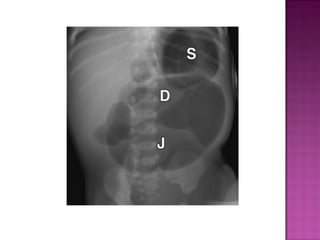

 Intestinal ischemiaduring intra uterine life.  Present with bilous vomitting & abdominal distention.

 Distention ofstomach ,duodenum & jejunum.